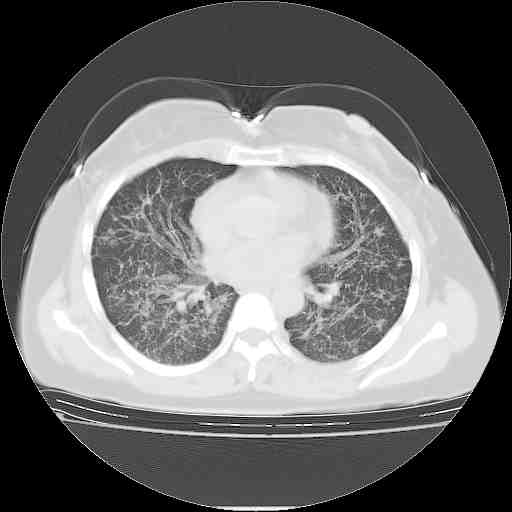

下面是今天刚刚做的,在上海治疗,吃了家属也说不清的一种药,一个月1万左右,

考虑  腺癌肺内转移,治疗较前病灶缩小、减少

肺癌并肺内转移,这种疾病治疗后在影像上看略有好转,不是很显著,但是肿瘤治疗效果影像只是一方面。

支持肺癌并肺内淋巴管炎,  原发灶小了,但转移较前片明显了.

支持右肺下叶周围型肺癌并肺内淋巴管炎,  原发灶小了,但转移较前片明显了.。

标准的细支气管肺泡癌呀!治疗后病情有所控制,也没治愈的迹象!

支持右肺下叶周围型肺癌并肺内淋巴管炎;病灶有所控制。

应该是比较典型的细支气管炎,4个月的时间不说明问题;有时候疾病是有个相对稳定期的,如果喝10元一斤的茶叶估计也会这样。